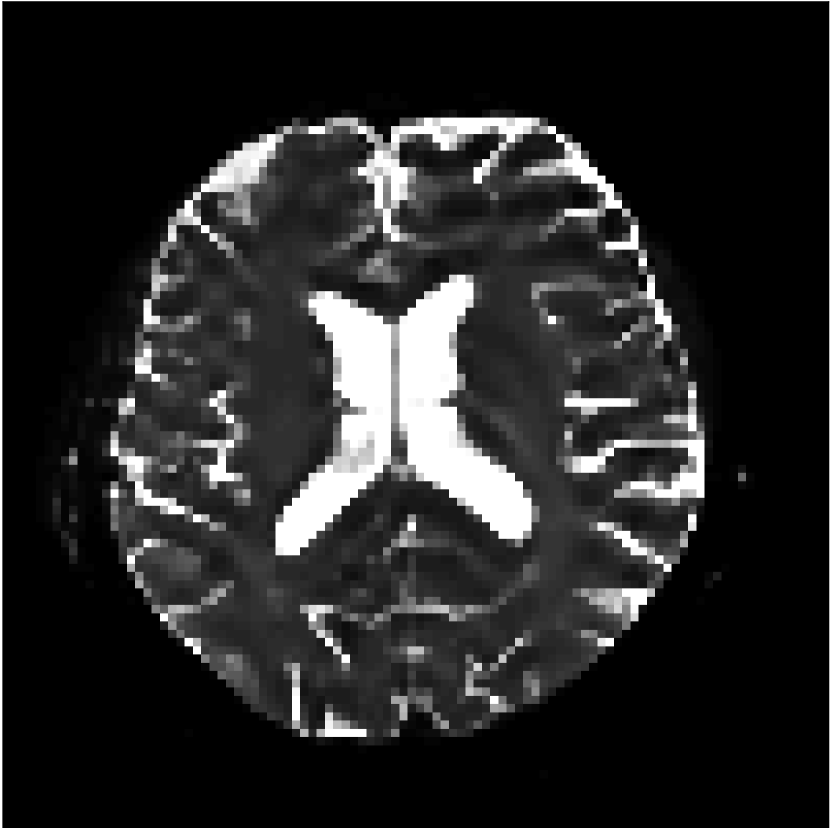

Figure 9 shows parameter maps for the different methods without partial Fourier (No PF) and with 5/8ths partial Fourier (5/8 PF). Mean diffusivities calculated from the raw DWI data (Raw) show notable noise and Gibbs ringing artifacts, while this is substantially removed with the state-of-the-art (SoA) method. However, the state-of-the-art method begins to lose its ability to compensate for the Gibbs ringing and resolution loss when partial Fourier is utilized in the acquisition. The effects of partial Fourier increases are primarily evident in the enlargement of the lateral ventricles and the presence of black lines in the vicinity of the lateral ventricles. The MCNN model is able to compensate somewhat for the ringing effects, but begins to introduce substantial artifacts at the 5/8ths partial Fourier factor, whereas the CCNN model continues to give high-quality mean parameter maps across all PF factors.

Raw

SoA

MCNN

Standard PF

CCNN

s/mm2

No PF

MD, m2/ms

5/8 PF

FA

MK

Similar trends are observed in the other diffusion parameter maps.